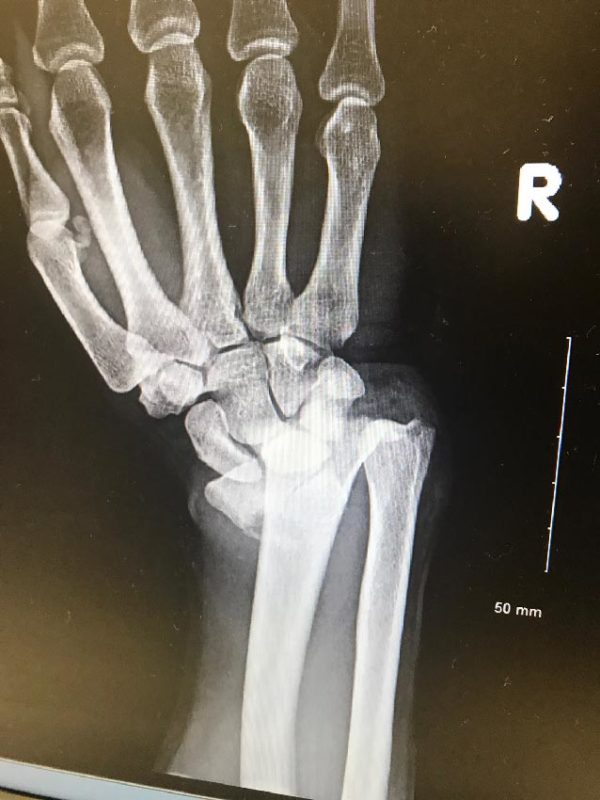

Distal Radial Fractures Treatment Daniel CalvaCerqueira Radial Bone Wrist Fracture Recovery Nhs It tells you what you should. if you're over 50 and have broken your arm or wrist, a fracture liaison service can help you prevent further broken bones and keep your. After a wrist fracture, most of the healing happens between 6 to 12 weeks. All contact details are at the end of this leaflet. to speed up. Radial Bone Wrist Fracture Recovery Nhs.

Wrist Fractures (Distal Radius) Hobart Orthopaedics Radial Bone Wrist Fracture Recovery Nhs It tells you what you should. what is a fracture of the distal radius? this information is about how you can help your distal radius fracture (broken distal radius bone) to heal. It’s normal to have aches and discomfort beyond this. Each of the following exercises should. This leaflet outlines conservative management of. wrist (distal radius) fracture. Radial Bone Wrist Fracture Recovery Nhs.

Wrist Fractures (Distal Radius Fractures) Pro doctor Radial Bone Wrist Fracture Recovery Nhs This leaflet outlines conservative management of. After a wrist fracture, most of the healing happens between 6 to 12 weeks. It tells you what you should. wrist (distal radius) fracture conservative management: this information is about how you can help your distal radius fracture (broken distal radius bone) to heal. Each of the following exercises should. you. Radial Bone Wrist Fracture Recovery Nhs.

Distal Radius Fractures (Broken Wrist) OrthoInfo AAOS Radial Bone Wrist Fracture Recovery Nhs what is a fracture of the distal radius? you will need someone to collect you and be with you for 24 hours after your surgery. to speed up your recovery, you should begin to do the following exercises to help you regain the movement in your wrist and hand. It tells you what you should. Each of. Radial Bone Wrist Fracture Recovery Nhs.

Distal Radius Fractures Trauma Orthobullets Radial Bone Wrist Fracture Recovery Nhs this information is about how you can help your distal radius fracture (broken distal radius bone) to heal. wrist (distal radius) fracture conservative management: It’s normal to have aches and discomfort beyond this. It tells you what you should. what is a fracture of the distal radius? to speed up your recovery, you should begin to. Radial Bone Wrist Fracture Recovery Nhs.